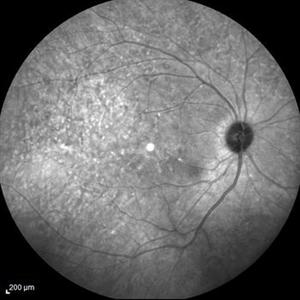

Late Stage Stargardt's Disease Late Stage Stargardt's DiseaseMar 13 2013 by Hamid Ahmadieh, MD Autofluorescence imaging of the right eye of a 46-year-old man with decreased VA due to advanced Stargardt's disease. Photographer: Nayereh Hadipoor, Negah Eye Center, Tehran Imaging device: Heidelberg Spectralis Condition/keywords: autofluorescence imaging, Stargardt disease